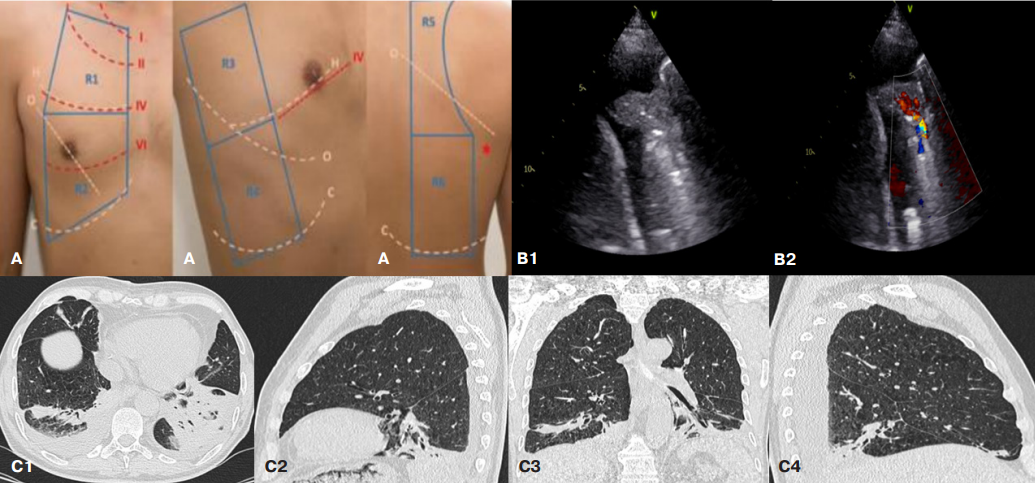

- Представленные клинические случаи демонстрируют возможности ультразвукового исследования легких с цветным допплеровским картированием для диагностики нозокомиальной пневмонии после коронарного шунтирования.

- Профиль консолидации легочной ткани размерами >20 мм с усиленным легочным кровотоком наряду с проявлениями синдрома системной воспалительной реакции перспективен в качестве критерия послеоперационной нозокомиальной пневмонии.

Введение. До настоящего времени не разработаны диагностические критерии нозокомиальной пневмонии после открытых операций на сердце, чувствительность и специфичность общепринятых критериев не изучена, их наличие может быть обусловлено рядом других причин, связанных с хирургической травмой. Рентгенологическое исследование лёгких не всегда выявляет данное осложнение на фоне послеоперационных изменений органов грудной клетки. Фокусное ультразвуковое исследование лёгких с использованием режима цветного допплеровского картирования представляется перспективным методом верификации пневмонии у данной категории пациентов, не уступающим компьютерной томографии.

Краткое описание. Представлены три клинических случая применения ультразвукового исследования, демонстрирующих характерные и нехарактерные для нозокомиальной пневмонии изменения паренхимы лёгких.

Дискуссия. Фокусное ультразвуковое исследование лёгких с цветным допплеровским картированием кровотока является информативным и безопасным лучевым методом диагностики пневмонии у пациентов, перенёсших открытое хирургическое вмешательство на сердце.